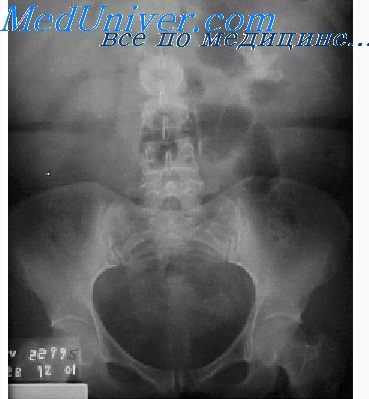

При ирригоскопии с тугим контрастированием кишечник равномерно заполнен барием, гаустры четко видны. После удаления бария кишка спадается, на снимках слизистая оболочка имеет правильную перистую структуру. При исследовании с двойным контрастированием кишечник равномерно растянут за счет воздуха, слизистая оболочка покрыта тонким слоем бария, позволяющим четко рассмотреть ее рельеф. При изменении положения тела во время исследования барий скапливается на нижележащей поверхности кишечной стенки под действием силы тяжести.

Хотя в большинстве случаев рак толстой кишки локализуется в ректосигмоидальной зоне и наилучшим способом его диагностики является ректороманоскопия, рентгенологическое исследование тем не менее позволяет выявить аденокарциному, а также, хотя и не столь часто, саркому вышележащих отделов толстой кишки. На снимках рак толстой кишки характеризуется дефектом наполнения с четкой границей между неизмененной и некротизированной слизистой оболочкой; если он циркулярно сужает просвет кишки, то рентгенологически напоминает яблочный огрызок. Эти признаки помогают отличить рак толстой кишки от диффузных поражений при воспалительных заболеваниях, но для уточнения диагноза необходима эндоскопии с биопсией.

Рентгенологическое исследование позволяет выявить воспалительное заболевание кишечника (например, дивертикулит, язвенный или гранулематозныи колит) и определить распространенность поражения. Для язвенного колита характерно появление первых признаков заболевания в анальной зоне с последующим проксимальным распространением поражения. При гранулематозном колите заболевание начинается со слепой и терминального отдела подвздошной кишки, а затем переходит на нижележащие отделы. Для уточнения диагноза необходима биопсия кишки. Кроме того, с помощью ирригоскопии можно диагностировать мешотчатые аденоматозные полипы, ворсинчатые опухоли на широком основании и другие органические поражения толстой кишки, такие как инвагинация, заворот сигмовидной кишки, синдром раздраженной кишки, нарушение мезентериального кровообращения и некоторые случаи острого аппендицита.